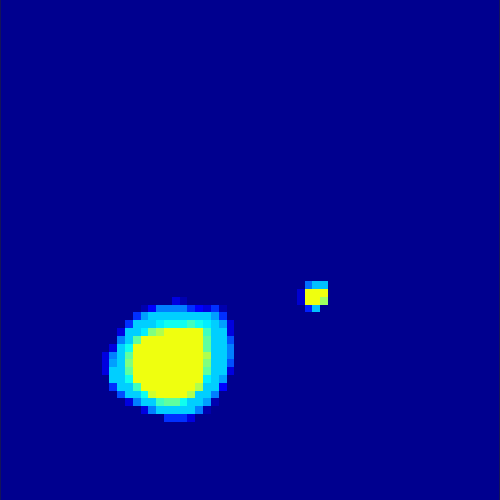

5.2 Monte Carlo Simulation

In order to test the behaviour of the proposed method in a more realistic, random-based test case, we performed a Monte Carlo simulation for dynamic SPECT imaging. First, we created a simple image phantom consisting of an outer and two inner circles which represents the structure of the region of interest (see figure 8(a)). Within those regions we assumed concentration curves over a time period of 90 time steps as displayed in figure 8(b). Based on the tracer intensity in an image frame at each time step, we created a variable number of random decay events (where the number is proportional to the average concentration in one pixel in the whole image frame per time step) with a probability proportional to the concentration in every subregion. They are detected by a virtual double head gamma camera rotating around the patient by 46 degrees per time step, which consists of 374 detector bins. Every simulated decay event is projected onto the scanner and counted by the corresponding detector bin.

In two different tests we fixed the number of events counted by the detector equal to (resp. ) times the average concentration in one pixel. The resulting sinogram images of the accumulated counts in each bin are shown in figure 9.

Based on the sinogram data we applied the proposed algorithm in order to reconstruct the original image sequence. The results for both test cases are shown in figure 10.

As one can see, the method is able to reconstruct the regions properly, even in case of a low count number. Within a number of iterations (average of 100 outer and 10000 inner iterations), the algorithm presents a reasonable reconstruction of the region of interest and the corresponding regional tracer concentration curves. Here, the parameters were not optimized as in the case of the synthesized data sets in the previous section, but kept fixed as , and . With futher optimized parameter values one could possibly provide even better results.